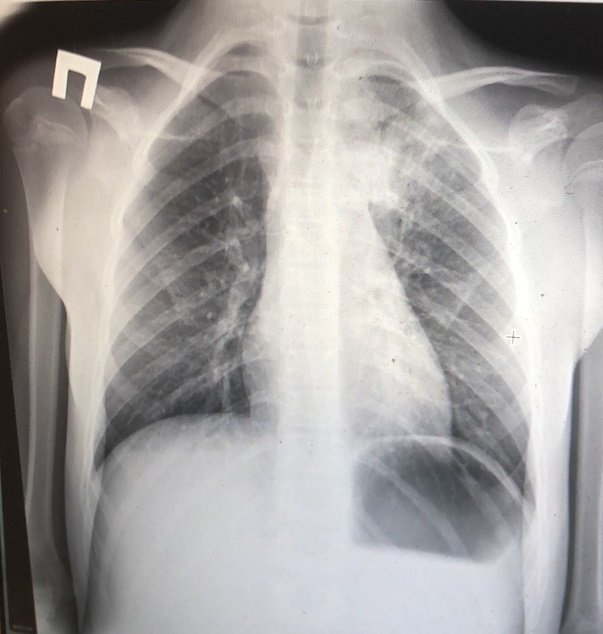

На рентгеновском снимке пневмония выглядит следующим образом:

Пневмония может развиваться в течение нескольких недель, а инкубационный период COVID-19 составляет 2-5 суток.

Атипичная пневмония на рентгеновском снимке:

Вирусная пневмония на рентгеновском снимке выглядит следующим образом:

Рентген снимок атипичной пневмонии

Атипичная пневмония — собирательный термин, включающий инфекционно-воспалительные поражения тканей лёгких. Причинами являются нехарактерные возбудители — микоплазма, хламидия, легионелла, вирусы. Воспаление лёгких протекает с повышением температуры, одышкой, общим недомоганием.

Диагностировать патологический процесс можно при помощи рентгена. Так, для микоплазменной формы характерна неоднородная инфильтрация лёгочной ткани, она может определяться слабо или быть среднеинтенсивной.

При легионеллезной, на снимке видно уплотнения (инфильтраты) округлой формы, локализующиеся на поверхности одной доли лёгкого. В ряде случаев наблюдается слияние инфильтратов.

У 25% пациентов одновременно с пневмонией определяется плеврит, с незначительным скоплением секрета в плевральной полости.

Правосторонняя бронхо- пневмония

Практически невозможно отличить пневмонию Legionella от других, основываясь на таком методе обследования. Присутствие легионеллы или хламидии подтверждается серологическим анализом крови.

Отдельное внимание стоит уделить воспалению неинфекционной этиологии. Одна из таких форм — инфаркт-пневмония, развивающаяся на фоне тромба, попавшего из лёгочной артерии в лёгкое. На рентгеновском изображении выступает как очаговое поражение с относительно чётким контуром.

Другой тип неинфекционного воспаления лёгочной ткани — аспирационный. Причиной выступает содержимое пищеварительного тракта, попавшее в дыхательные пути. Этот тип патологии характеризуется многообразием симптомов, которые имитируют различные заболевания лёгких.

Как правило, на снимке однородный очаг, контуры относительно чёткие. С целью контроля лечения аспирационной пневмонии рекомендуется проходить повторный рентген.

Как выглядит заболевание на рентгеновском снимке

Признаки воспаления лёгких на снимке называют «затемнениями», отображаются они белым цветом, поскольку само изображение является негативом.

Пятна и рентген-признаки:

- До 3 мм — мелкоочаговые.

- До 7 мм — среднеочаговые.

- До 12 мм — крупноочаговые.

- От 12 мм и более — фокусные.

Пневмония на снимке, в частности затемнения, характеризуются следующим образом:

- Распространённые. Визуализируют в пределах одного сегмента.

- Субтотальные. Затемнение большей части поля органа или нескольких сегментов.

- Тотальные. Патологический процесс охватывает всю область лёгочной ткани. Сильная пневмония слева